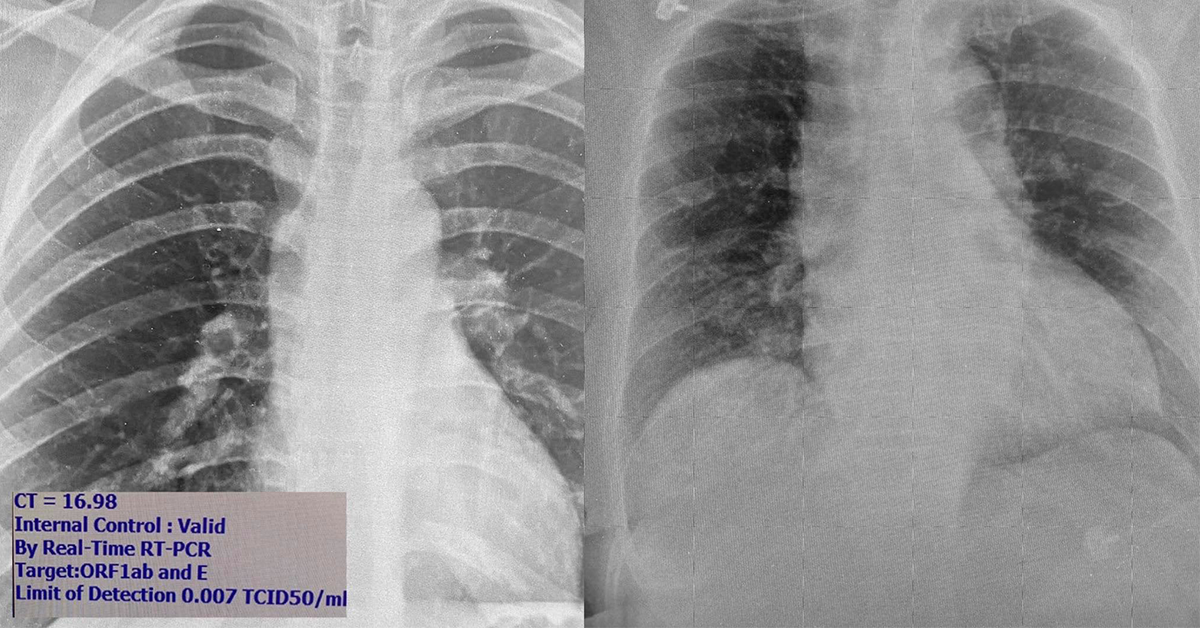

ทั้งนี้หมอยังได้อธิบายภาพที่อยู่ทางด้านขวาว่า เริ่มเห็นคนไข้มีอาการไข้หวัดหรือปอดอักเสบมาที่โรงพยาบาล แต่ไม่ยอมบอกประวัติความเสี่ยงเพื่อปกปิดการเดินทาง แพทย์อาจไม่ได้ส่งตรวจหาโควิด เพราะคิดว่าเป็นปอดอักเสบจากเชื้ออื่นที่พบได้บ่อยกว่า

ดังนั้นถ้ามีประวัติไปที่เสี่ยงตัองแจ้งแพทย์เสมอเพื่อแยกออกไปจากคนไข้คนอื่นที่มีโอกาสติดแล้วมีอาการรุนแรงหรืออาจติดต่อไปยังหมอและพยาบาล

เมื่อวาน (2 ม.ค.) มีคนไข้เป็นปอดอักเสบมาตรวจ แต่ไม่ยอมบอกประวัติความเสี่ยงแต่แพทย์เห็นฟิล์มผิดปกติเหมือนปอดอักเสบจากไวรัสเลยส่งตรวจโควิดและตรวจเจอเชื้อ พอเค้นซักประวัติอีกรอบถึงยอมรับว่าไปบ่อนมา ซึ่งเป็นบ่อนใน”กรุงเทพ”

โชคดีที่ดักเคสนี้ได้เร็ววินิจฉัยได้เร็ว การไม่บอกประวัติเสี่ยงอาจทำให้บุคคลากรทางการแพทย์อาจติดโควิด เพราะในบางครั้งถ้าการดูแลรักษาอาจต้องใช้การพ่นยาการใช้ออกซิเจนทำให้เชื้อกระจายฟุ้งในโรงพยาบาล โรงพยาบาลอาจจะขาดกำลังแพทย์พยาบาลเพื่อรักษาคนไข้อื่น